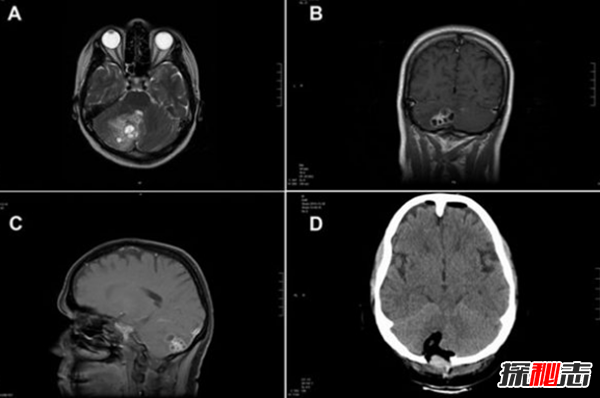

5、脑内绦虫

罗斯玛丽·阿尔瓦雷斯以为她得了脑瘤,当医生们去做手术时,发现她的脑干上有一条绦虫。医生拿掉了它,最后她完全康复了。很明显,她吃了被人类粪便污染的食物后体内产生了蠕虫。